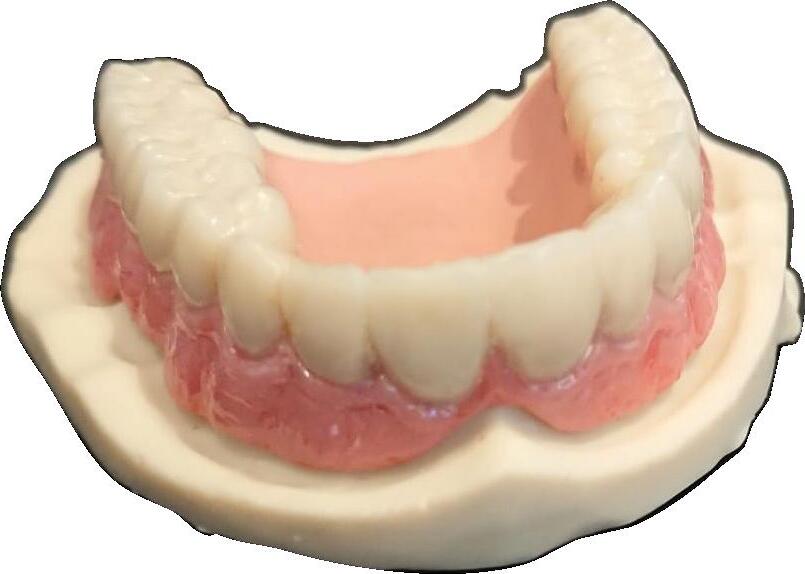

ția clinică, de la restaurarea unui singur dinte până la reabilitarea arcadelor, cu ajutorul tratamentului SKY fast & fixed se poate observa formarea de os nou. Înălțimea crestei alveolare se păstrează cu ajutorul osului nou format în zona conică inversată, deoarece există o indicație redusă pentru regularizarea osoasă a sitului implantar. Conceptul de creștere osoasă reprezintă exact etapa următoare de dezvoltare a platform switch: designul implantului și al bontului, conul inversat microstructurat și poziționarea subcrestală a implanturilor copaSKY acționează sinergic nu numai pentru a preveni resorbția osoasă, dar și pentru a sprijini regenerarea osoasă.

Studiile și experiența clinică au demonstrat faptul că prin poziționarea subcrestală a implantului copaSKY se poate obține mai mult spațiu în zona gingivală pentru atașarea țesutului moale și remodelarea țesutului osos.

Rezultate clinice impresionante Rezultatele observate de către clinicieni sunt convingătoare. Indiferent de indica-

Conceptul de Creștere Osoasă

• Zona conică inversată – oferă mai mult spațiu pentru os și țesut conjunctiv

• Suprafața microstructurată –sprijină oseointegrarea și atașarea țesutului conjunctiv

• Poziționarea subcrestală – susține creșterea/regenerarea osoasă